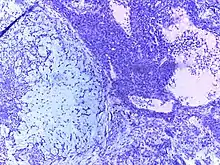

![]() | Squamous cell carcinoma of cervix | Invasive Squamous Carcinoma of the Cervix. Cold Knife Cone. | Category: Histopathology of squamous cell carcinoma of the cervix | Invasive squamous carcinoma of cervix |